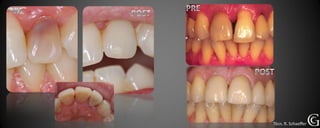

Salud Gingival

Antes de comenzar cualquier tratamiento, debemos lograr un control de la

placa dental, para que las encías estén en salud. Esto se logra, corrigiendo la

higiene del paciente de ser necesario y en el consultorio eliminando la placa

mineralizada la cual no es eliminada por el cepillado.

Salud Gingival Antesde comenzar cualquier tratamiento, debemos lograr un control de la placa dental, para que las encías estén en salud. Esto se logra, corrigiendo la higiene del paciente de ser necesario y en el consultorio eliminando la placa mineralizada la cual no es eliminada por el cepillado.